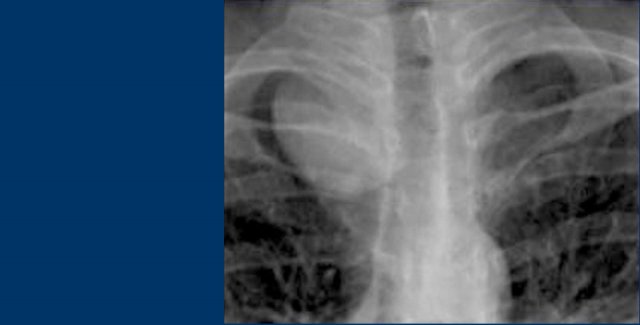

On the PA film there is a lobulated widening of the superior mediastinum.

On the lateral chest film the retrosternal clear space is obliterated.

This happened to be a patient with lymphoma.

On the left FDG-PET images of the same patient.

There are multiple lymphatic masses in the anterior, middle and even posterior mediastinum, spreading to the neck.